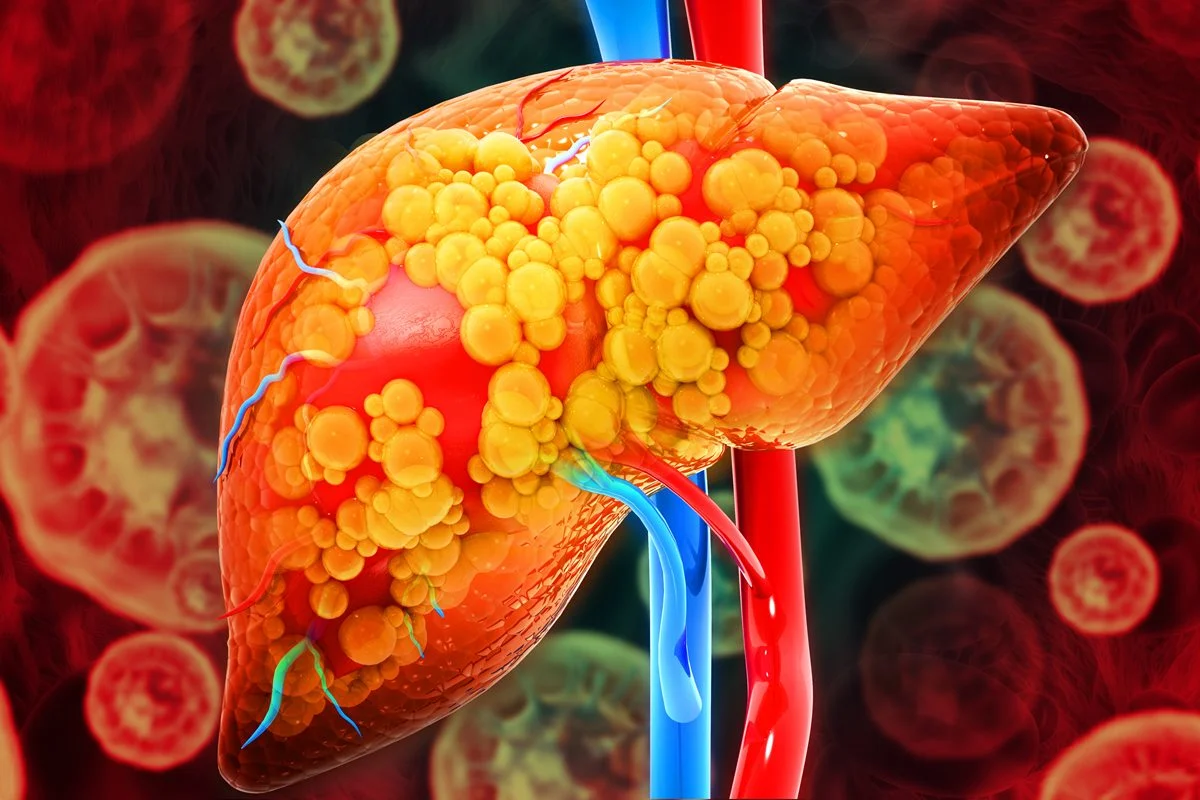

A esteatose hepática é popularmente conhecida como gordura no fígado

Mohammed Haneefa Nizamudeen/Getty Images

A condição de gordura no fígado acomete 30% da população mundial, segundo o artigo

Magicmine/Getty Images

No início, as manifestações costumam ser inespecíficas, como cansaço, fraqueza, perda de apetite, náuseas, sensação de inchaço abdominal ou desconforto do lado direito do abdome

Magicmine/Getty Images